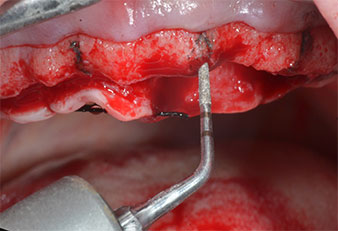

Abb. 1: Präoperative Ansicht des Kieferkamms, die Implantatpositionen wurden mithilfe einer Kunststoff-Bohrschablone markiert. Wegen des niedrigen Kieferkamms sind im Seitenzahnbereich sehr kurze Implantate geplant.

Implantatpositionen